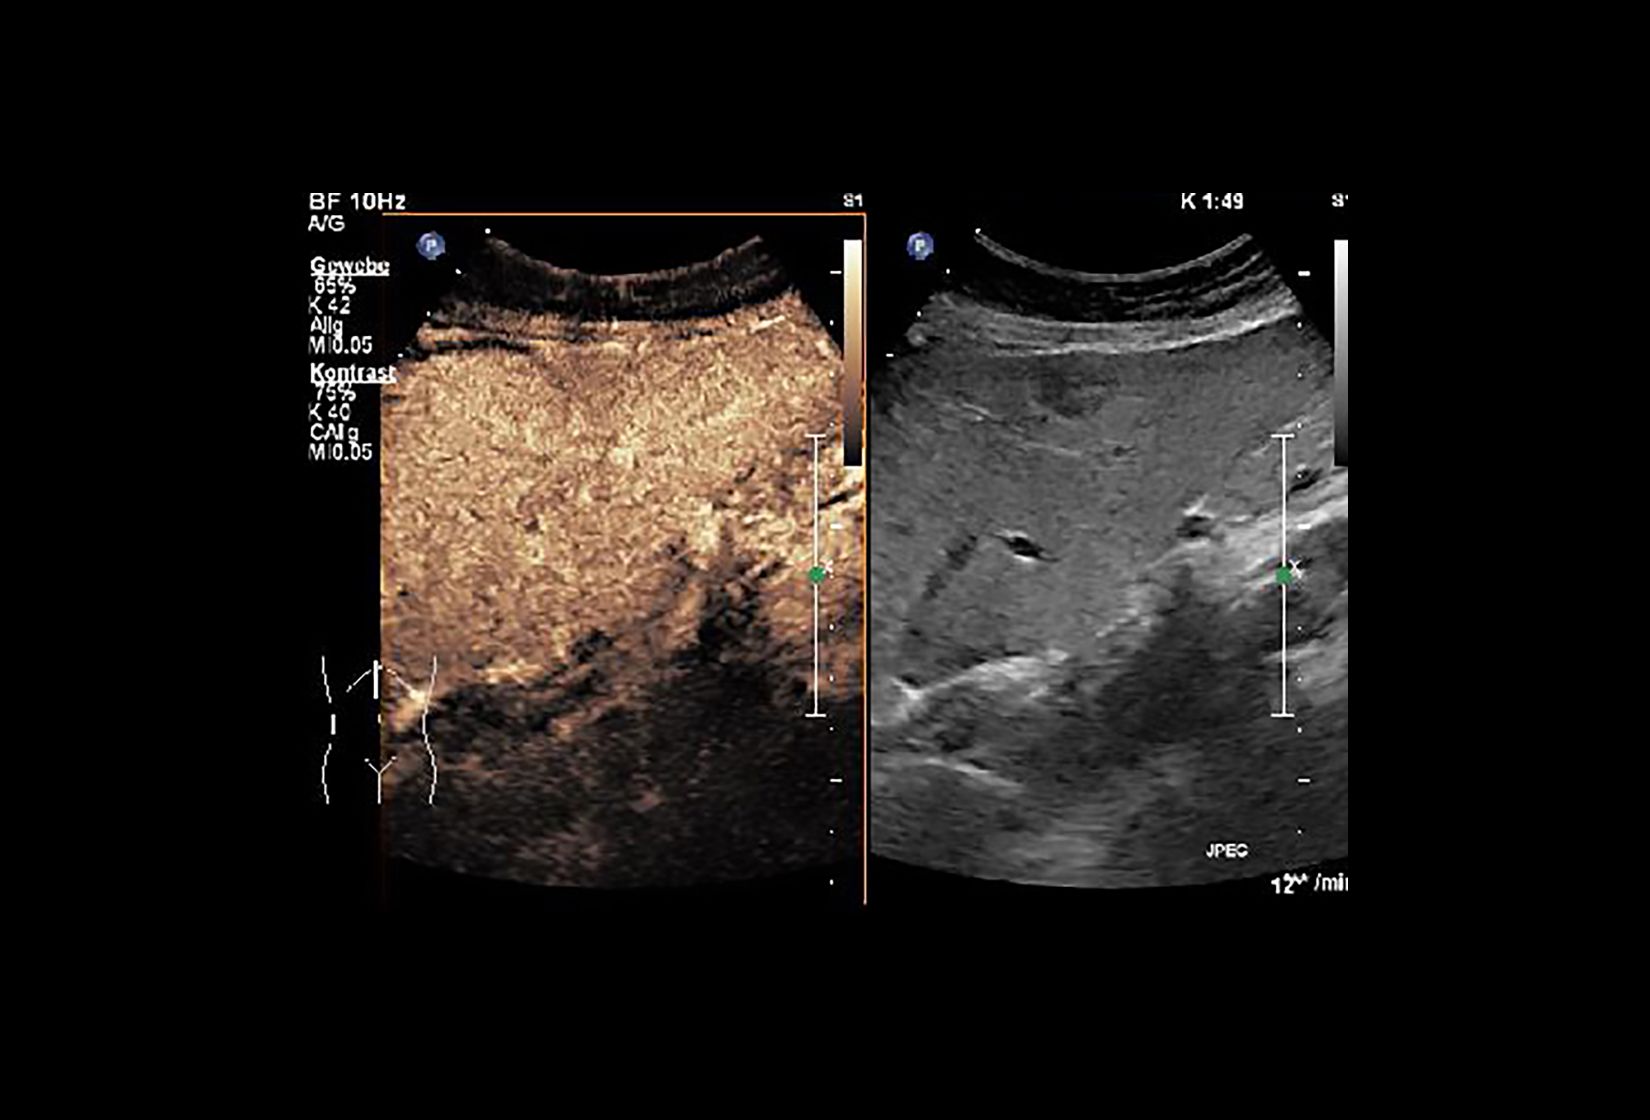

Die Sonographie – oder auch Ultraschall – ist eine Methode der Bildgebung, die ausschließlich mit Schallwellen arbeitet und so keinerlei Strahlenbelastung für den Patienten bedeutet. Ausgestattet mit modernen Hochleistungsgeräten ist es so oft möglich mit einer hohen Ortsauflösung auch kleinste Strukturen ohne Röntgenstrahlen darzustellen. Neben der Gefäßdiagnostik kommt die Sonographie regelmäßig zur Untersuchung des Abdomens (Bauchraum), des Thorax (Brustkorb), der Extremitäten sowie der Schilddrüse zum Einsatz. Das Leistungsspektrum umfasst zudem die kontrastmittelgestützte Sonographie u.a. zur Abklärung von Leberherden, oder aber auch von Endoleaks (bei Patienten mit Gefäßendoprothesen). Zudem wird die Sonographie im Rahmen aufwendiger Prozeduren in der Angiographie als zusätzliche Orientierungshilfe eingesetzt.